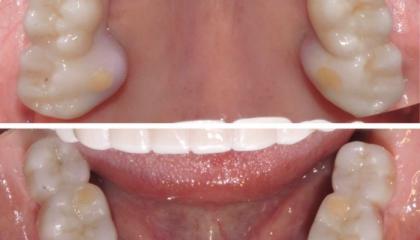

Zirconia bridge on Southern DC Implants

Tooth Replacement

Zirconia Implants